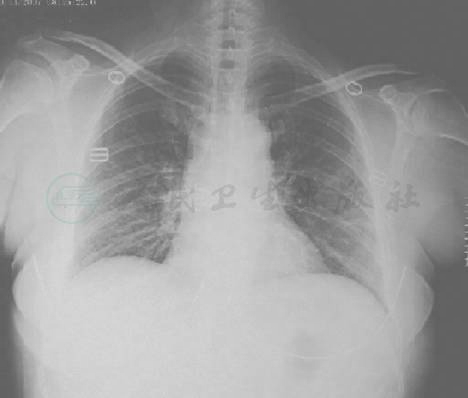

一般状况差,呼吸急促,32次/分,发热面容,口唇轻度发绀,皮肤及巩膜轻度黄染,未见皮肤出血点及皮疹,浅表淋巴结未触及肿大。咽部充血,双侧扁桃体轻度肿大,表面有脓苔。颈部略有抵抗,双肺叩诊呈清音,呼吸音粗,可闻及散在湿啰音,无胸膜摩擦音。心律齐、心率102次/分,心音正常,各瓣膜区未闻及病理性杂音。腹平软,无压痛,肝脏肋下可及,无明显触痛,脾脏未触及。实验室检查:血常规:WBC 2.0×109/L,RBC 4.59×1012/L,Hb 131g/L,PLT 48×109/L;肝功能:ALT 105U/L,AST 125U/L,TBIL 47.5μmol/L,DBIL 35.8μmol/L,LDH 820U/L;肾功能正常;HIV抗体阴性,肥大反应阴性;动脉血气分析:pH 7.38,PaO2 6.93kPa,PaCO2 4.27kPa,SaO2 85%,氧合指数172。胸部CT平扫显示双肺磨玻璃影及条索状影(图2)。

图2 胸CT(10月12日)示双肺弥漫的磨玻璃影及条索状影

4.肺部病变先为纹理增粗,条索状改变,继之为间质性变化,进行性加重,形成大片浸润和实变,双肺均衡受累,双上肺明显。抗感染、抗病毒、抗曲霉及激素治疗无效,病变迅速扩散;